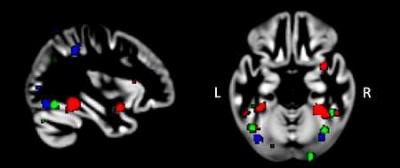

distribuzione regioni attive cervello autismo